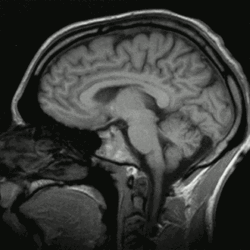

Patrick Spät – ein Vertreter des Panpsychismus – hält die funktionalistische Begründung hingegen für unvollständig: Sie kann zwar die Übertragung physischer Reize auf artspezifische Verhaltensweisen erklären, doch diese könnten genauso gut nichtbewusst ablaufen wie bei einem Computer. Der von einem Lebewesen erlebte „Bewusstseinsstrom“, dessen Erhaltung bei uns Menschen 20 % der Körperenergie beansprucht, obwohl das Gehirn höchstens 3 % des Körpergewichtes ausmacht, wird damit nicht erklärt. Spät fragt, warum es bewusste Vorgänge gibt (die auch unbewusst ablaufen könnten) und wo der evolutionäre Vorteil liegt, der diesen großen Energieaufwand rechtfertigt.[6]